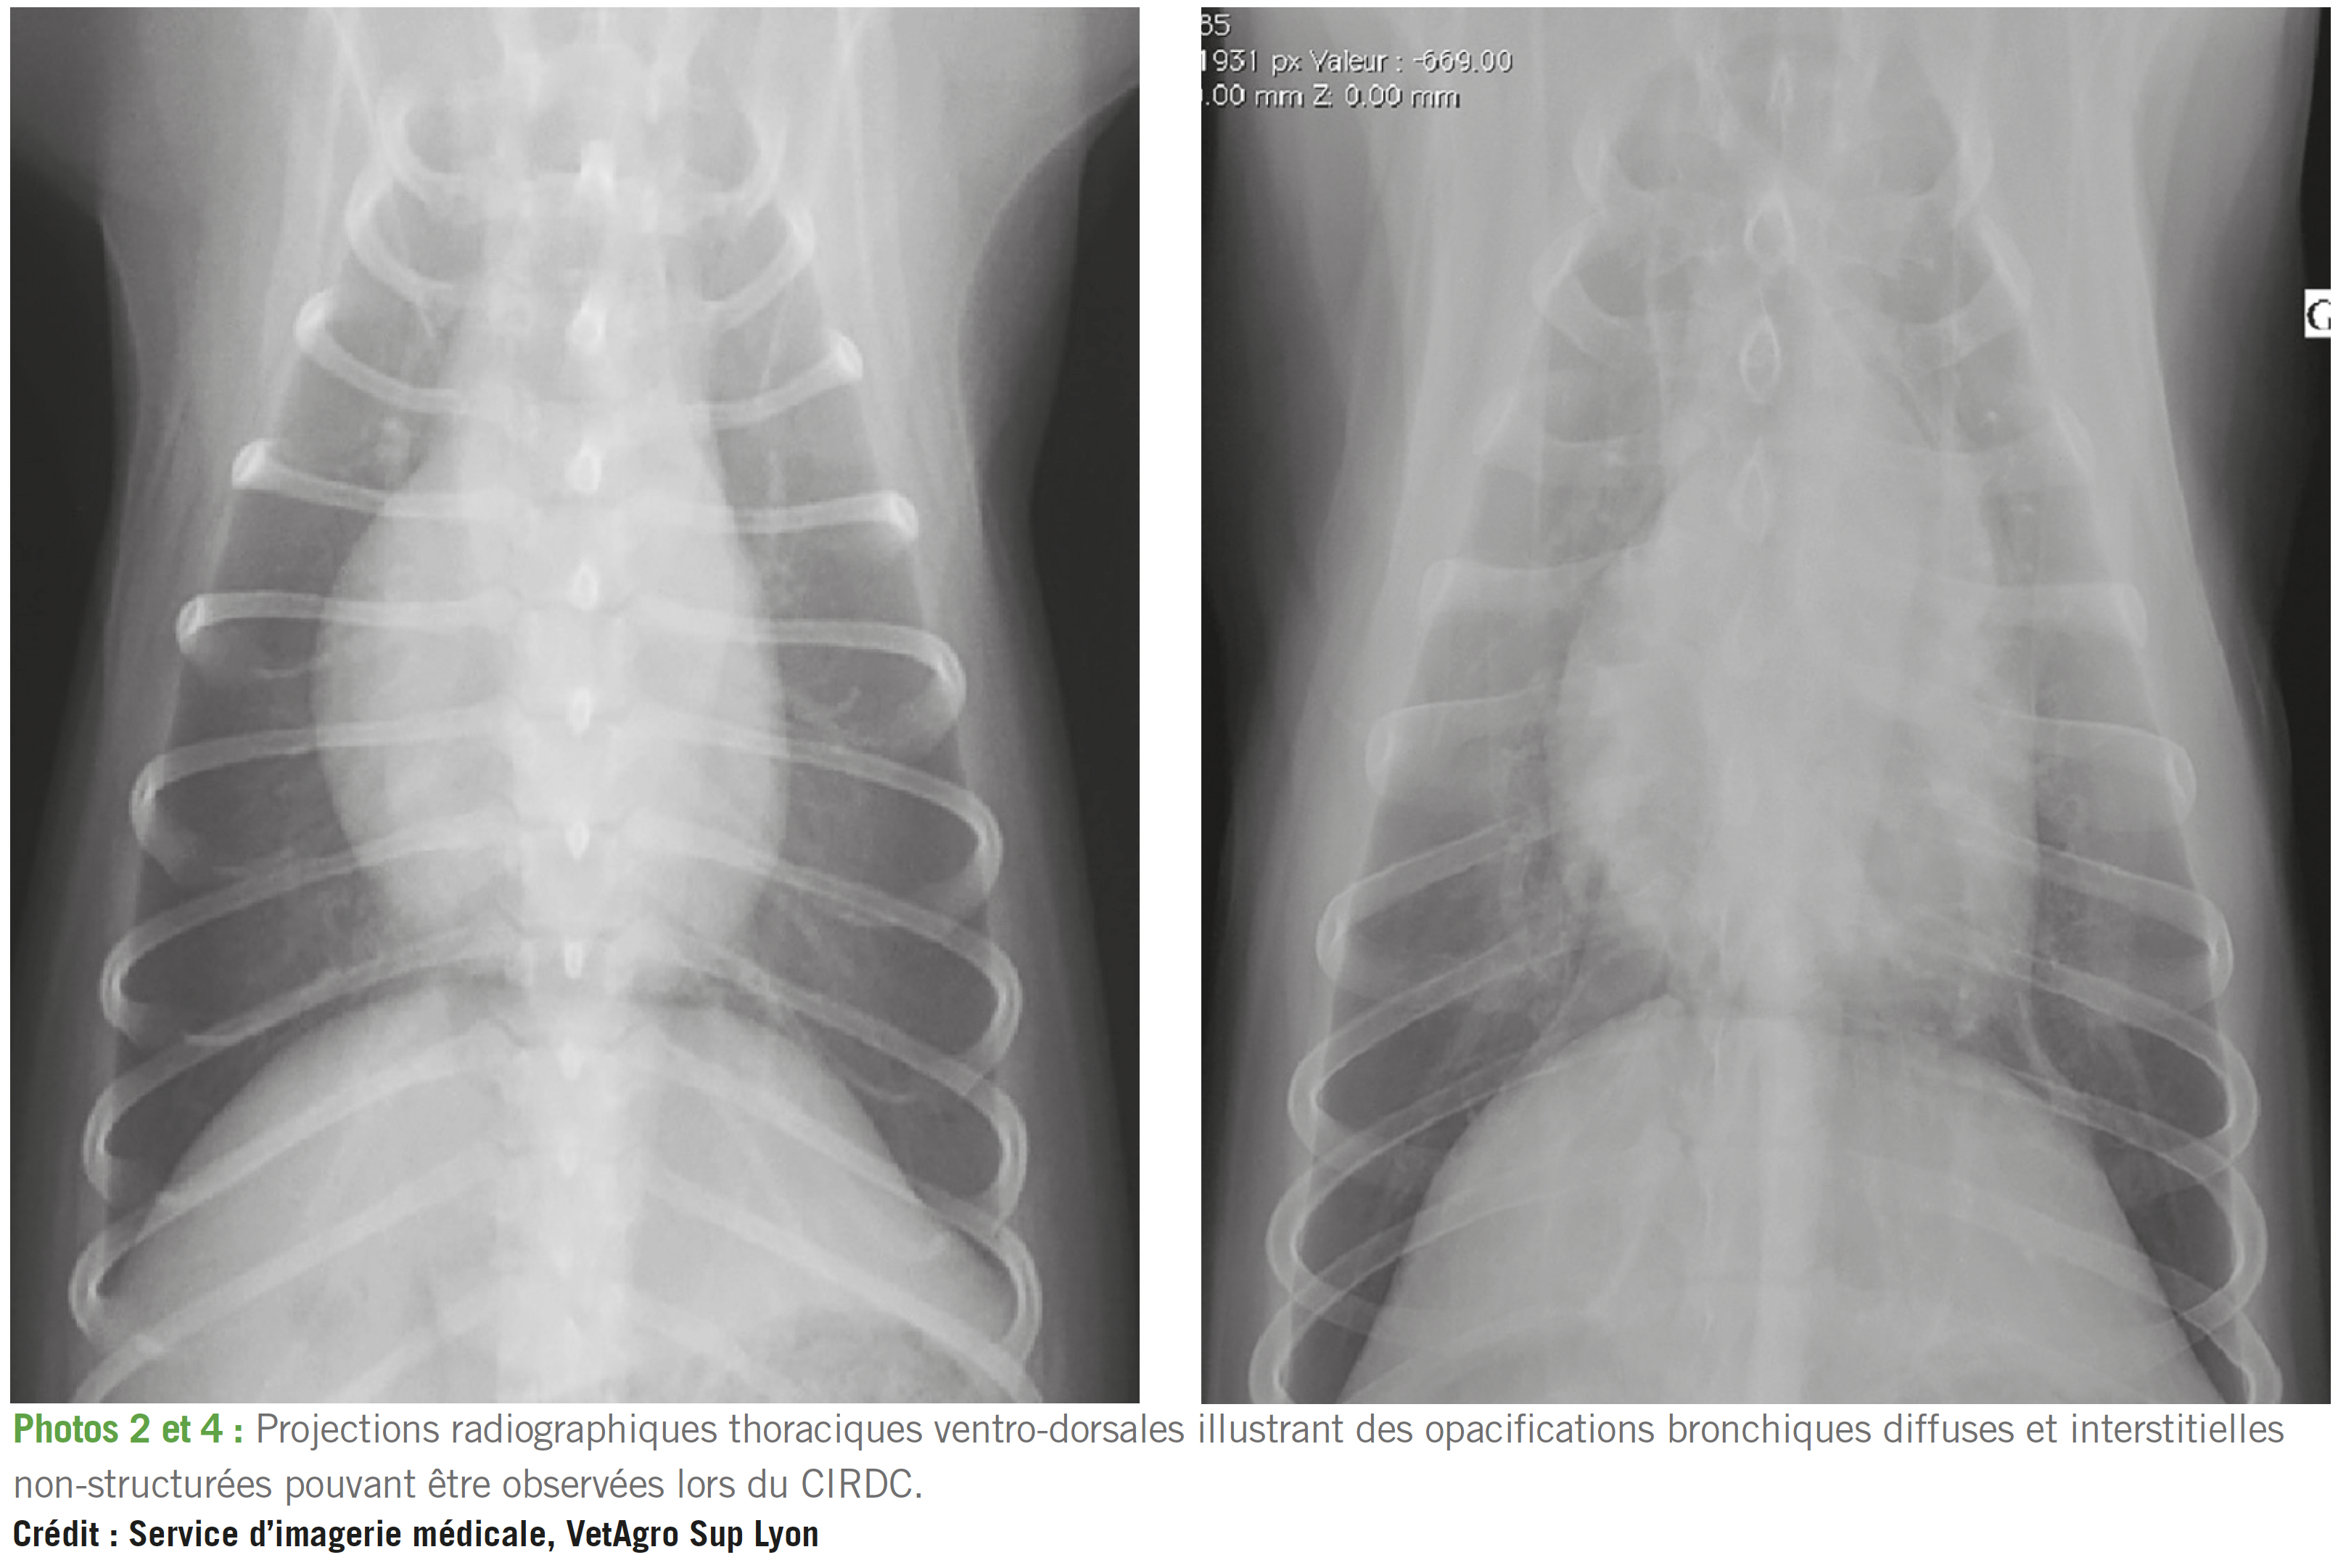

En l'absence de réponse rapide aux antitussifs, anti-inflammatoires et antibiotiques, et en cas de dégradation générale et respiratoire (détresse respiratoire), des radiographies thoraciques peuvent devenir utiles, afin de préciser le type et l'étendue des lésions (cf. photos 2 à 5). Une opacification radiographique bronchique diffuse est rencontrée dans virtuellement 100 % des trachéo-bronchites infectieuses canines 1-4,14.

Cependant, cette anomalie n'est pas spécifique et l'intérêt de la radiographie thoracique s'explique principalement dans ce contexte par la nécessité de rechercher des lésions qui aggravent ou entretiennent la toux (foyers alvéolaires notamment).